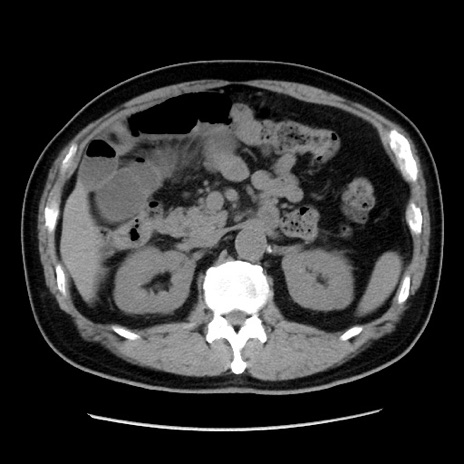

症例16(横断像)

【症例】 70歳代男性

【主訴】 腹痛、嘔吐

【現病歴】 約1ヶ月前より間欠的に腹痛と嘔吐あり、当院消化器内科を受診したところCTで多発する肝臓のLDAを指摘され、精査中であった。以降は消化器症状は安定していたが、2日前より嘔気と腹痛があり、同日より排便・排ガスが消失した。改善認めず、 本日、救急外来を受診した。

【既往歴】 大腸ポリープ切除後。

【身体所見】意識清明・会話良好、BT 36.3℃、BP 127/80mmHg、 P 80bpm、腹部:膨満あり、平坦・軟、上腹部正中および下腹部正中に圧痛あり、反跳痛なし、筋性防御なし。

【データ】WBC 7200、CRP 0.77